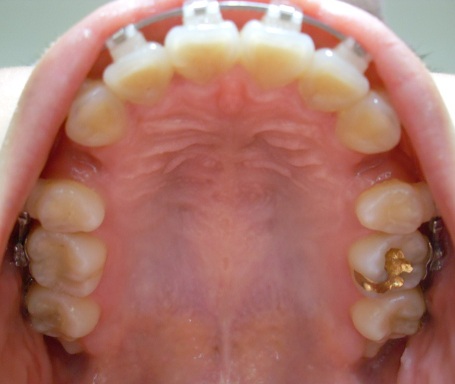

상악사진볼까용?!?!? ^.^

뒤에 사랑니 조콤초콤 나는거 너므 귀엽다능ㅋㅋㅋㅋㅋ